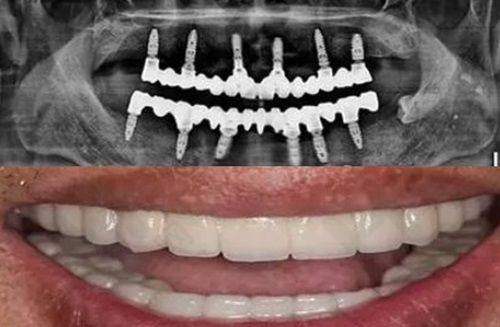

另一个特色项目是即刻微创种植。传统的牙齿种植需要先拔牙,等待伤口愈合后再进行种植手术,这不仅增加了患者的痛苦,还延长了治疗周期。而义乌德维口腔的即刻微创种植技术则实现了即拔即种,大大减少了患者的痛苦。

在拔牙的同时,医生会立即将种植体植入牙槽骨内,避免了二次手术的麻烦。这种技术采用了微创的方式,手术创口小,出血少,术后修复快。患者在手术后当天就可以正常饮食和生活,不会对日常生活造成太大的影响。

即刻微创种植的价格为3580元/颗,性价比非常高。对于那些牙齿缺失的患者来说,这种技术为他们提供了一种更加便捷、效率高的牙齿修复方案。许多患者在接受了即刻微创种植手术后,都表示手术过程轻松,修复成效良好,对医院的技术和服务赞不绝口。

后来,他经朋友介绍来到了义乌德维口腔。医生为他进行了详细的口腔检查后,建议他采用即刻微创种植技术。在医生的耐心解释和安抚下,李先生终于放下了心中的顾虑,接受了手术。手术过程非常顺利,李先生没有感觉到太多的痛苦。术后,医生还为他制定了详细的护理方案,并定期进行回访。现在,李先生的牙齿已经修复得非常好,他又可以像以前一样正常饮食和微笑了。他对义乌德维口腔的技术和服务非常满意,还介绍了身边的朋友来这里看牙。